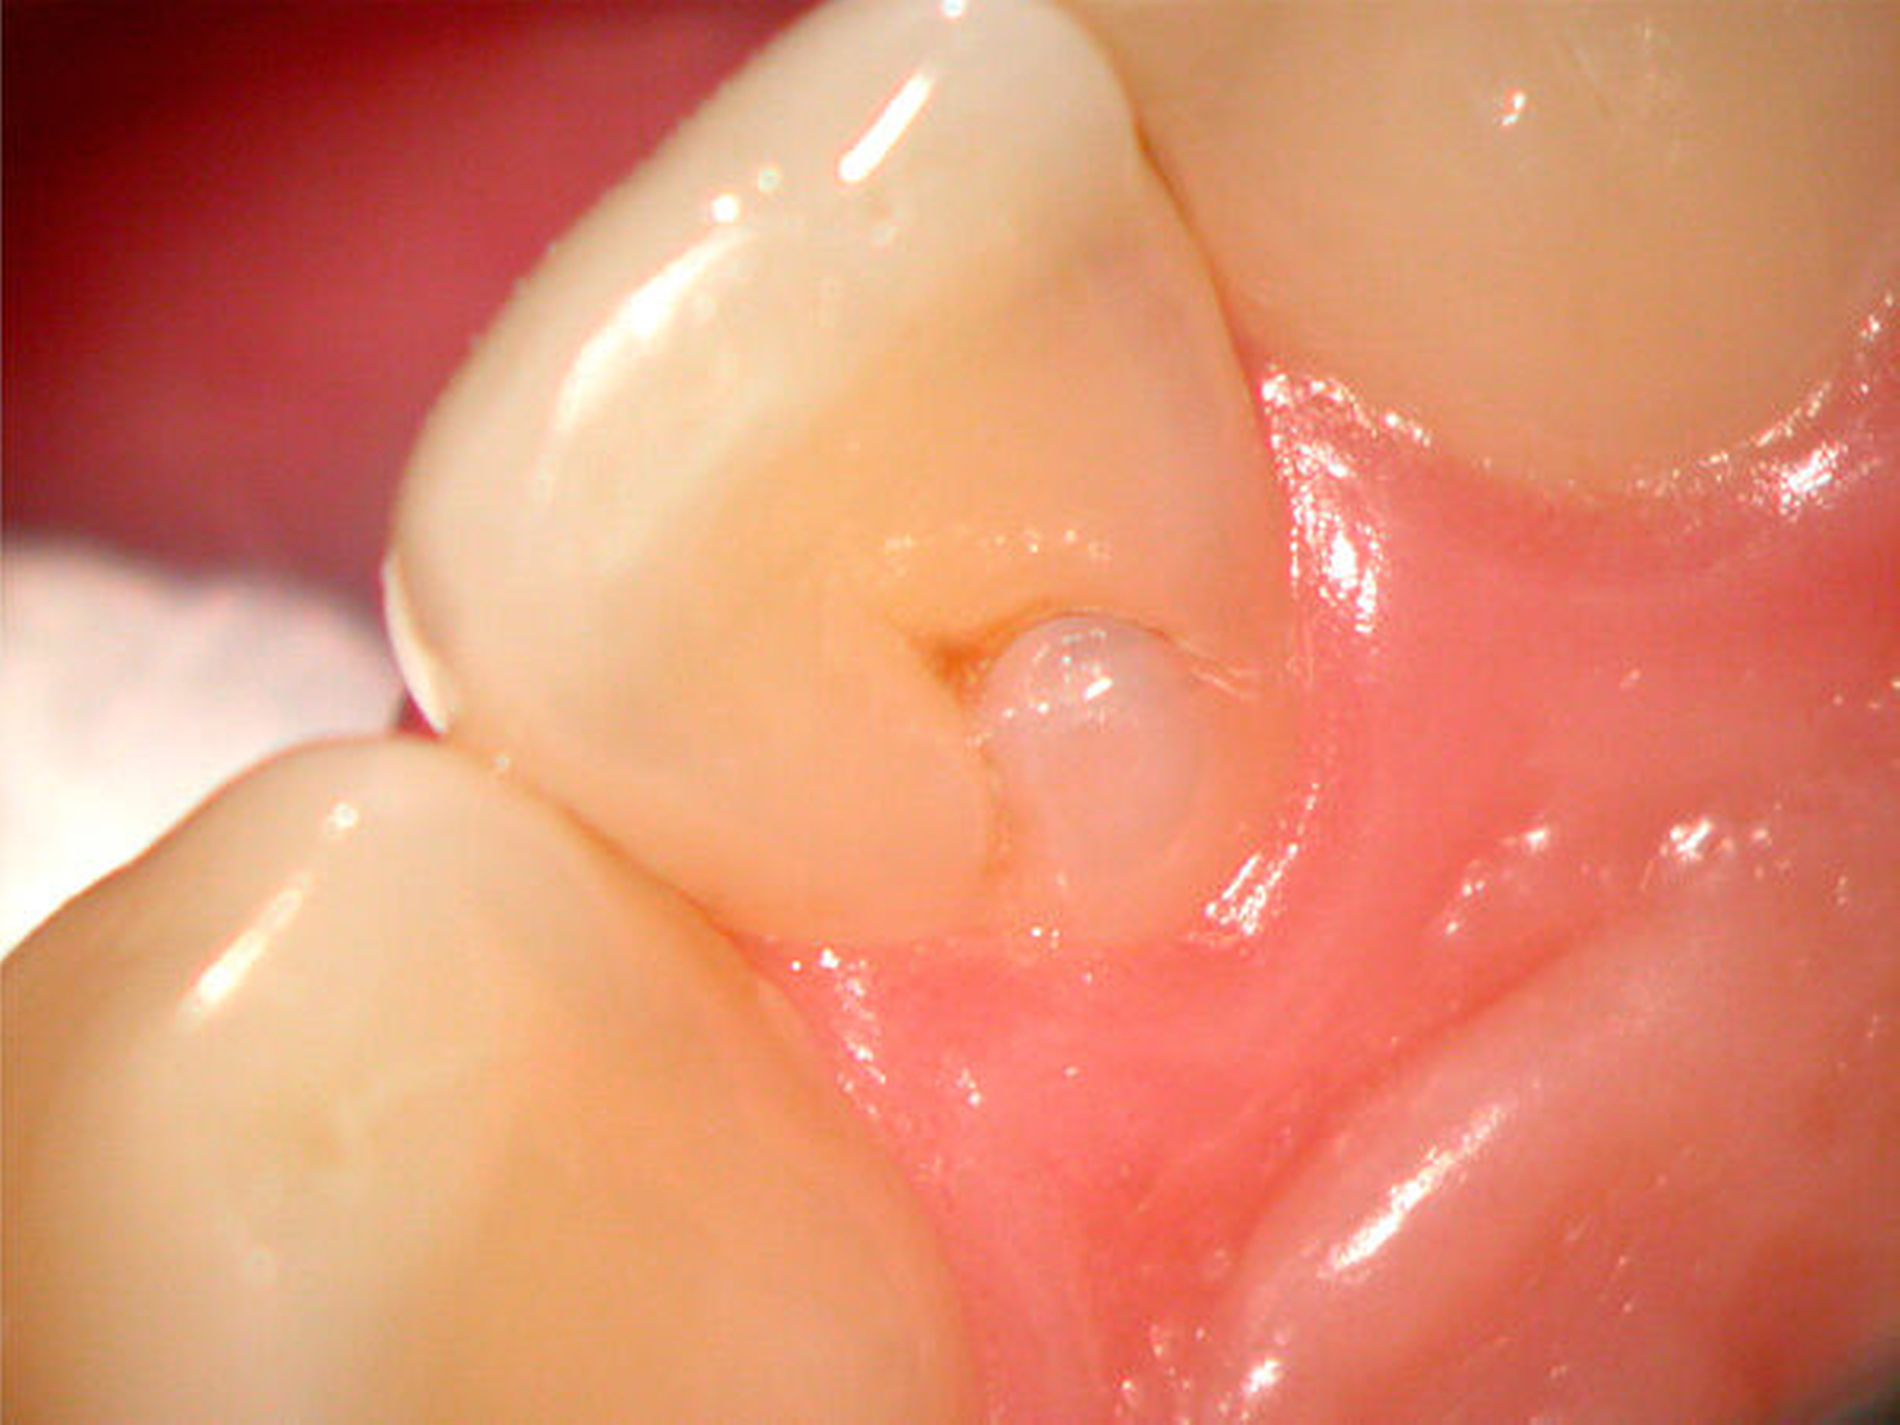

Zapfenförmige seitliche Schneidezähne können ein Hinweis auf eine abweichende Form des Wurzelkanalsystems sein. So können mehrfach gekrümmte Wurzelkanäle beobachtet werden. Darüber hinaus können auch Fehlentwicklungen des äußeren Schmelzepithels auftreten und als Ursache für scheinbar untypische pulpitische Beschwerden bei fehlender Karies verantwortlich sein (Abbildung 13). Invaginationen des äußeren Schmelzepithels können in unterschiedlich tiefer Ausprägung auftreten [Tomas, 1974]. Die Prävalenz dentaler Invaginationen liegt zwischen 3 und 10 Prozent, wobei sie in bis zu 70 Prozent der Fälle bilateral auftreten [Thomas, 1974; Gotoh, 1979; Hülsmann, 1995]. Nach Oehlers werden drei Grade unterschieden [Oehlers, 1957]. Insbesondere Typ-II-Invaginationen mit einer Einstülpung bis unterhalb der Schmelz-Zement-Grenze können bei mikrobieller Infektion aufgrund der Nähe zur Pulpakammer eine irreversible Pulpitis und eine nachfolgende Pulpanekrose auslösen. Im Fall eines Dens invaginatus vom Typ III besteht zwischen der Eintrittspforte an der klinischen Zahnkrone und dem apikalen Endpunkt ein vom Wurzelkanal unabhängiger Verlauf [Hülsmann, 1995]. Die Infektion eines Dens invaginatus kann deshalb röntgenologisch zu einer periapikalen Aufhellung bei fortbestehender Sensibilität des Zahnes führen (Abbildung 14). Eine minimalinvasive Invaginationstherapie kann den Erhalt der Pulpa ermöglichen (Abbildung15).

Eine entgegengesetzte Wachstumsrichtung des äußeren Schmelzepithels im Verlauf der Zahnentwicklung kann zum Auftreten von dornähnlichen Evaginationen führen (Abbildung 16). Besonders ausgeprägte Formen können vom Patienten als störend empfunden werden. Eine Einschleiftherapie führt in solchen Fällen zur Freilegung des pulpanahen Dentins, gegebenenfalls sogar zur Eröffnung der Pulpa und erfordert in jedem Fall einen dichten Verschluss mit Komposit oder sogar eine partielle Pulpotomie mit direkter Überkappung [Hülsmann & Schäfer, 2007].